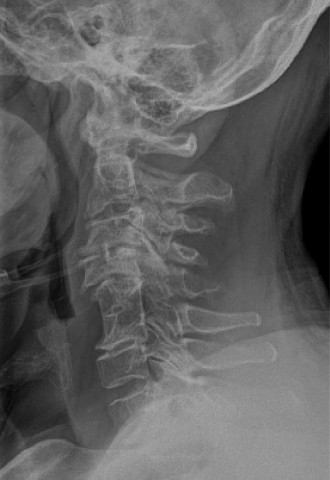

CASE 1 A 63-year-old male sustained a hyperextension injury to his neck while diving into a pool. Upon presen…